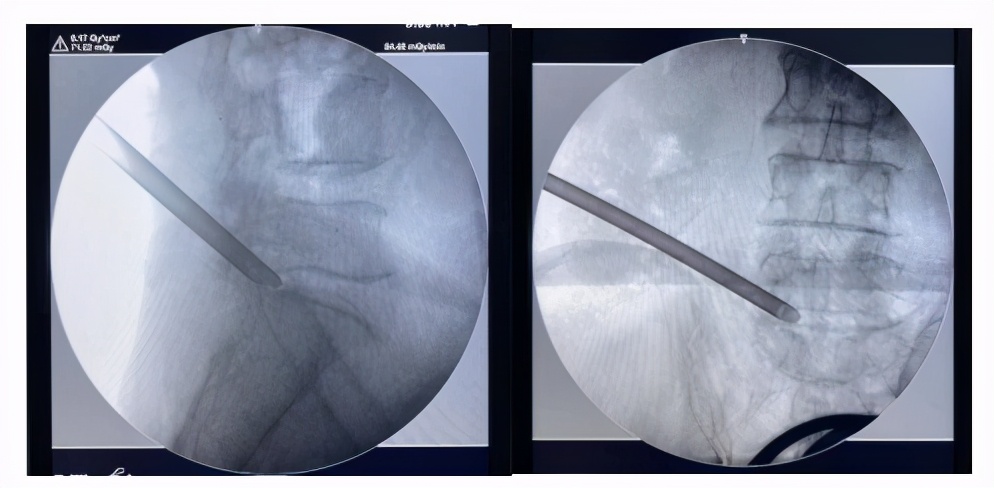

术中,主治医生为何阿姨行L1、L2、L3S神经根脉冲调控治疗,完全复制出疼痛症状。

由于何阿姨之前做过开放手术,腰部软组织瘢痕增生明显,正常结构紊乱,给穿刺过程带来极大的困难。